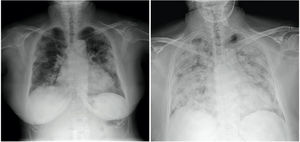

A 77-year-old patient weighing 70 kg and with hypertension and dyslipidaemia was admitted due to bilateral pneumonia (Fig. 1), with PCR positive for SARS-CoV-2. He was transferred to the Intensive Care Unit (ICU) due to refractory hypoxaemia that required orotracheal intubation and mechanic ventilation.

On the left, posteroanterior chest radiograph on admission, showing bilateral peripheral consolidations in upper, middle and lower fields, with no pleural effusion - findings suggestive of infection by COVID-19.

On the right, anteroposterior chest X-ray in decubitus 3 days after admission, prior to orotracheal intubation, showing radiological evolution of the disease.